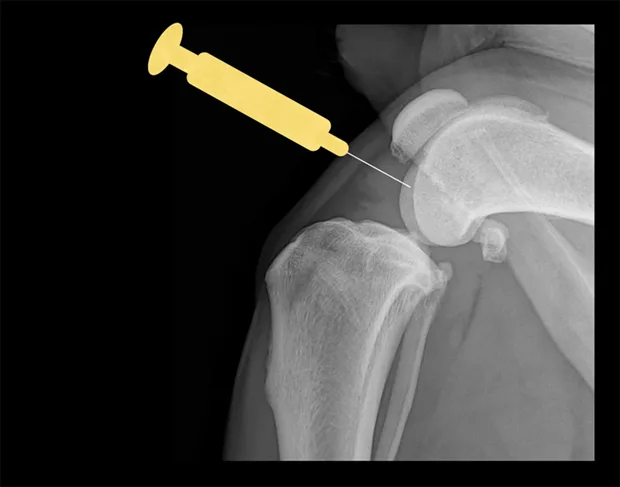

Shoulder

Place the patient in lateral recumbency with the shoulder joint in a neutral position. For large dogs, insert the needle about 0.5–1 cm distal to the acromion process of the scapula in a lateral-to-medial direction; a lateral radiograph of the shoulder joint may help determine the distance from the distal acromion to the joint space. The needle may need to be passed in a slightly dorsal direction to enter the joint. A 1.5-inch needle is adequate for even large-breed dogs.

Craniocaudal view of shoulder. Place needle just distal to the acromion (yellow dot), angled slightly dorsally.

Lateral view of shoulder. Insert needle just distal to the acromion (yellow dot).